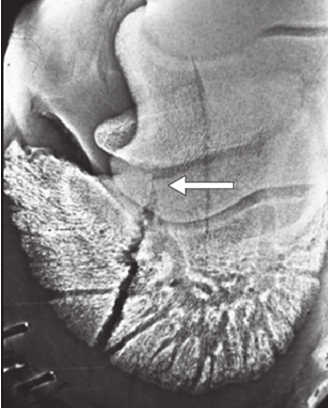

• what view is this image?

dorsoproximal palmarodistal 60 oblique view